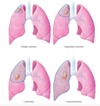

Adenocarcinoma (40%): lung peripheries

Squamous cell (20%): centrally and present with pneumonia due to bronchus obstruction

Large: metastasise early